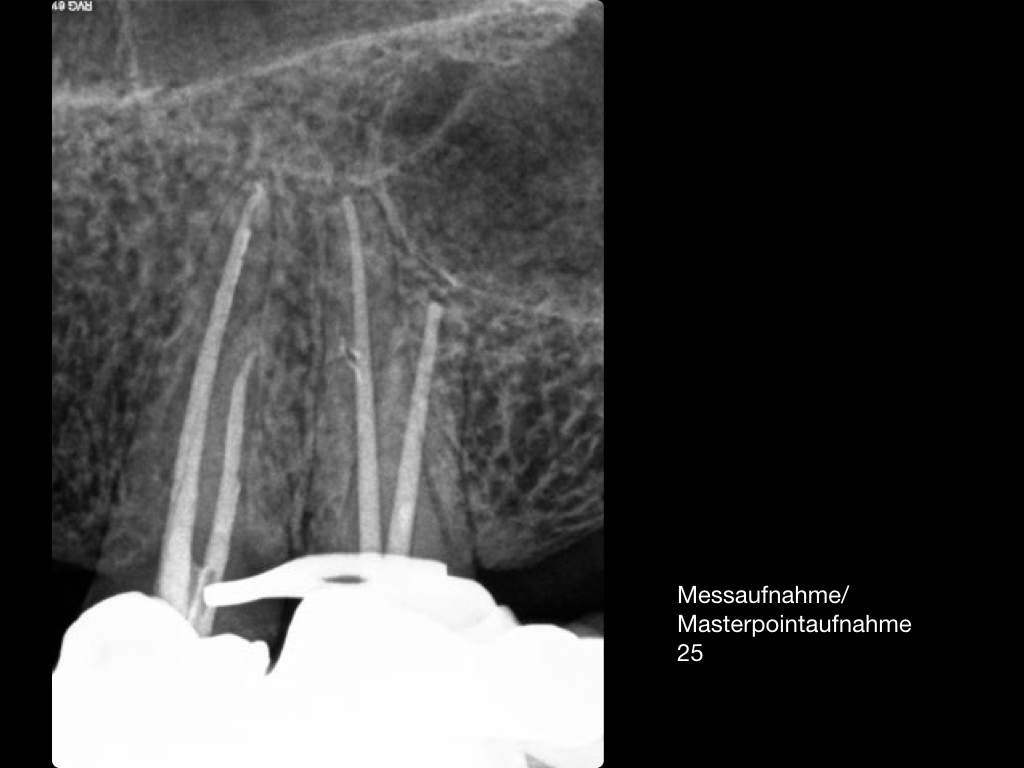

Es ist zu sehen … (2)